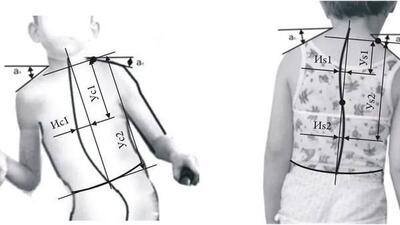

مدیر کل تربیت بدنی سازمان امور دانشجویان اعلام کرد: تقریبا ۵۰ درصد دانشجویان حداقل به یک اختلال اسکلتی عضلانی دچار هستند.

تقریباً 50 درصد از دانشجویان ایرانی حداقل به یک اختلال اسکلتی عضلانی دچار هستند. این آمار مربوط به دانشجویان جدید الورود است و نشان میدهد که کنکور ممکن است تغییرات قابل توجهی در سلامت و تندرستی دانشجویان ایجاد کند.